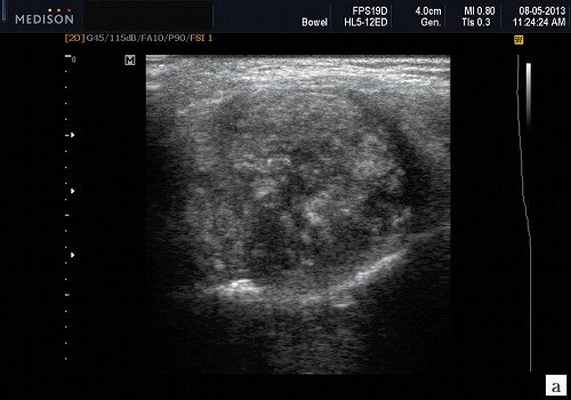

Сиаладениты - большая группа полиэтиологических воспалительных заболеваний СЖ (рис. 3). Первичные сиаладениты - сиаладениты, рассматриваемые в качестве самостоятельных заболеваний (например, эпидемический паротит). Вторичные сиаладениты - сиаладениты, являющиеся осложнениями или проявлениями других заболеваний (например, сиаладенит при гриппе). Эхографическая картина при разной этиологии малоспецифична. Этиология имеет клиническое значение в процессе определения тактики лечения.

Рис. 3. Сиаладенит правой поднижнечелюстной слюнной железы.

- обструктивные сиаладениты, развивающиеся при затруднении оттока слюны при обструкции выводного протока камнем (рис. 5-7) или сгустившимся секретом, а также вследствие рубцового стеноза протока. По распространенности процесса различают очаговый, диффузный сиаладениты и сиалодохит - воспаление выводного протока. Течение процесса может быть острым и хроническим;